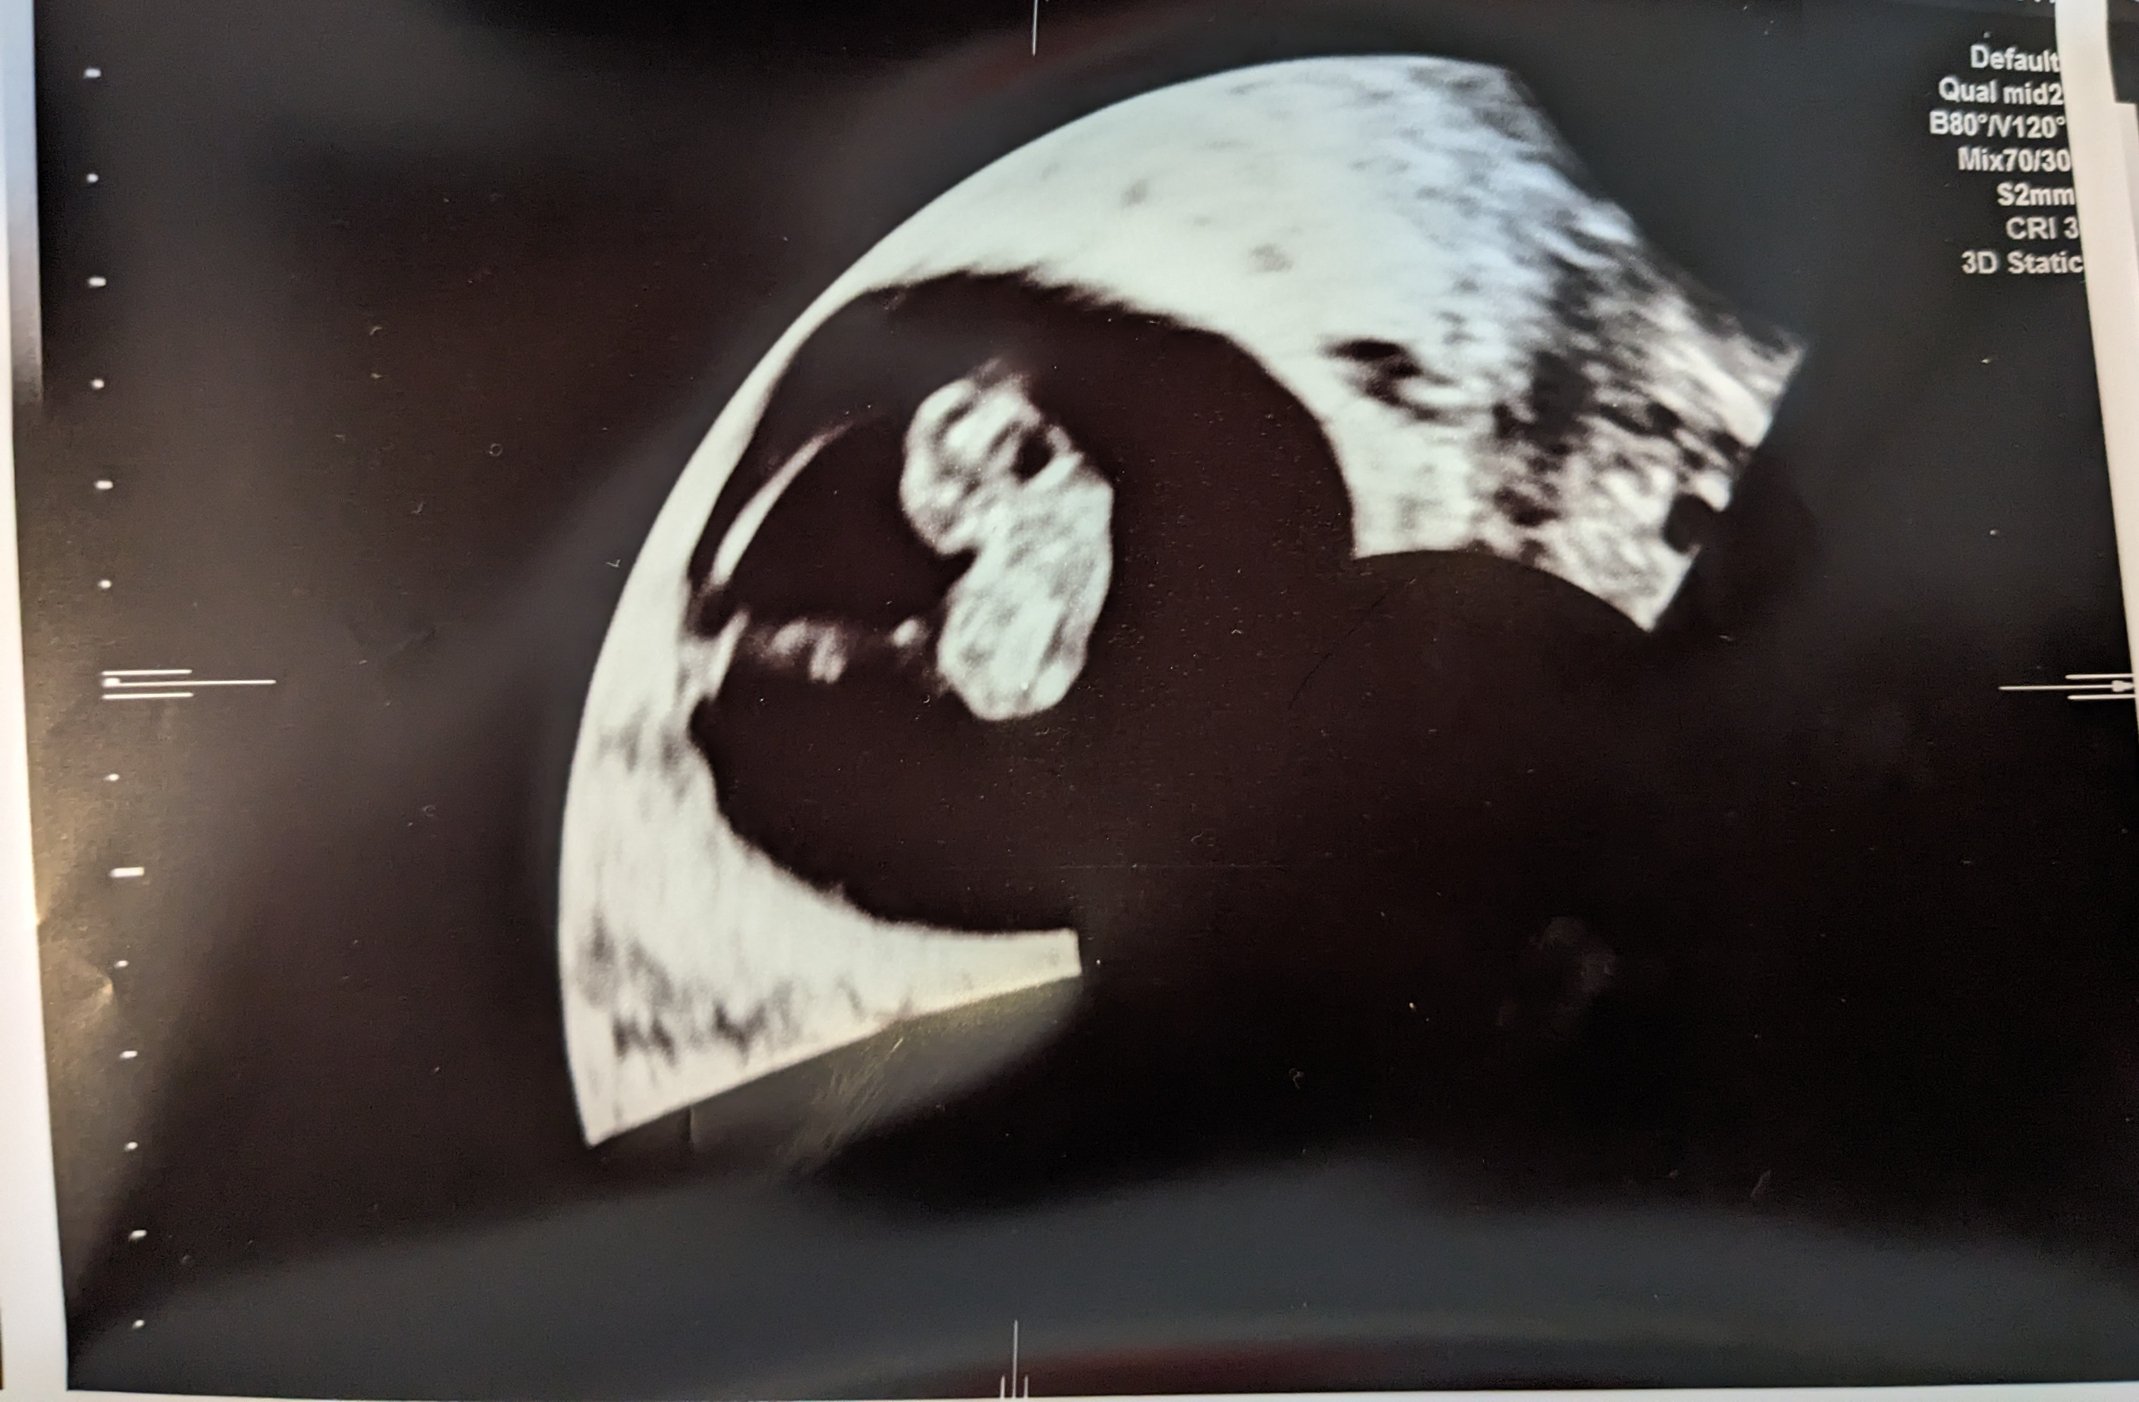

It's really real. They adjusted my due date by 1 day so I guess I'm now 9 weeks on the dot and due 11/2. Strong heartbeat at 178 bpm. Had a fun appointment explaining to all the new doctors that this is my 4th total pregnancy (2 viable, 1 mc) and we already have 4 kids. It took them a minute. 🤣

Crazy to see how big my uterus is in comparison lol.